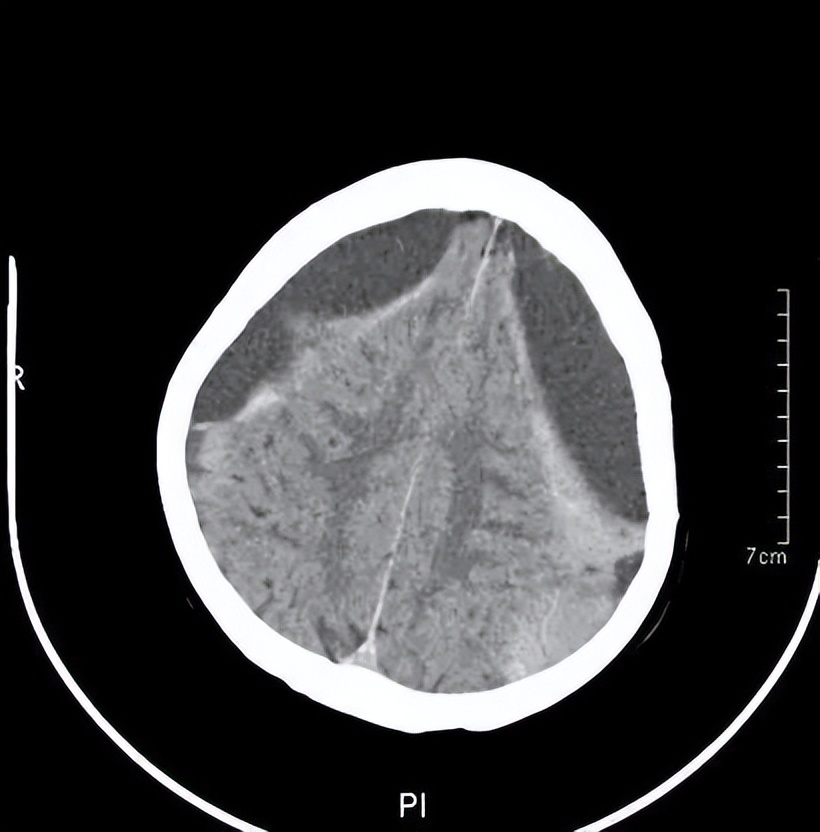

王阿婆门诊的头颅CT

黄主任询问了王阿婆的病史,给她做了简单的神经检查和认知测试,给王阿婆安排了急诊CT检查。结果显示,王阿婆的脑部有两处出血,报告为“双侧慢性硬膜下血肿”,需尽快神经外科住院治疗。神经外科建议王阿婆接受一个叫做“双侧钻孔引流”的手术。需在王阿婆的头部钻两个小孔,把血肿引流出来,手术并不复杂,但是需要专业的神经外科医生来执行。